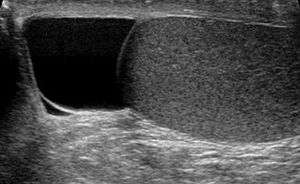

| Ultrasound of a testicle (grey) and a spermatocele (black). | |

Finding a painless, cystic mass at the head of the epididymis, that transilluminates and can be clearly differentiated from the testicle, is generally sufficient. If uncertainty exists, ultrasonography of the scrotum can confirm if it is spermatocele.